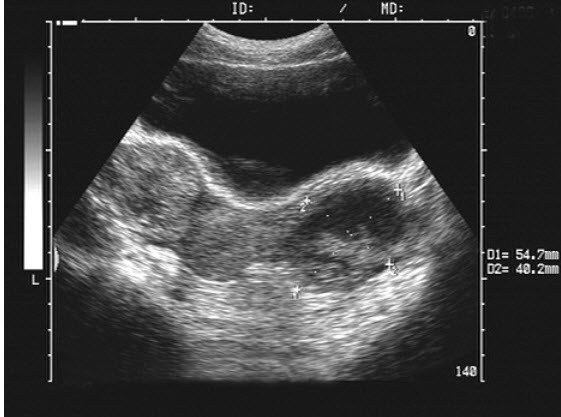

女性,29岁,人流术后三天,下腹疼痛。超声检查如图,最可能的诊断是()

A .炎性包块

B .黄体囊肿

C .盆腔血肿

D .囊腺瘤

E .畸胎瘤